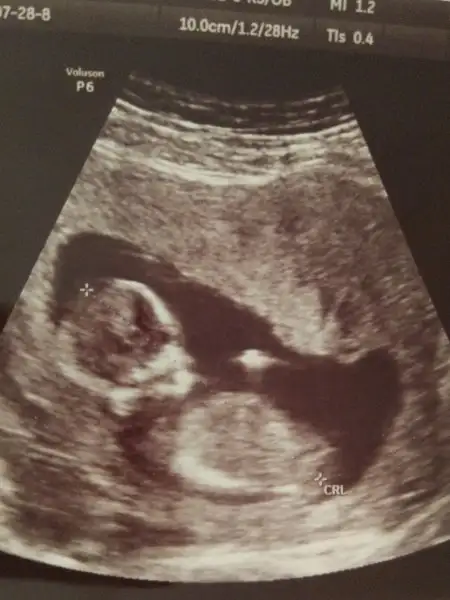

Bende geldim kizlar kontrolden. Burnu kemigi gozuktu. Ensede. 1.2 çıktı. Bence risk yok dedi doktor. Kan tahlilleri haftaya persembe cikacakmis :) ultrasonuda ekledim varmi cinsiyet tahmin etmek isteyen :)

Bende geldim kizlar kontrolden. Burnu kemigi gozuktu. Ensede. 1.2 çıktı. Bence risk yok dedi doktor. Kan tahlilleri haftaya persembe cikacakmis :) ultrasonuda ekledim varmi cinsiyet tahmin etmek isteyen :) Eki Görüntüle 2027293